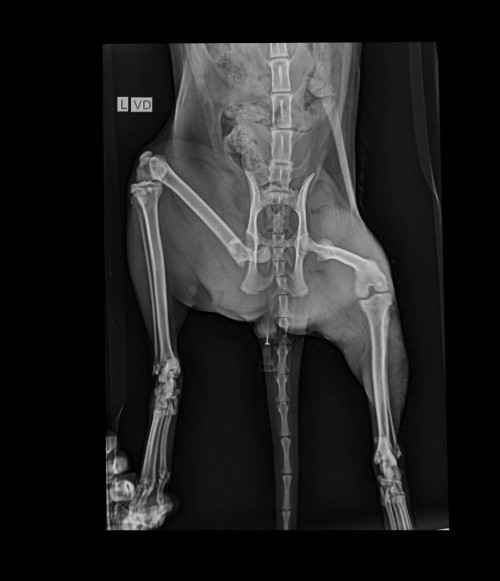

I have my cat which was missing for few days and then now i found him back but with his back leg limping.

we have done an x-ray and attached.

i have ask the doctor and the doctor told me that she needs to perform surgery whereby she will destroy that bone socket which got dislocated and let the muscle/ligaments to get hold of the rest of the bone.

furthermore, after the surgery, the cat needs to perform physio for couple of months to let the cat walk back as normal. even so, there is no guarantee that the cat can walk back as normal.